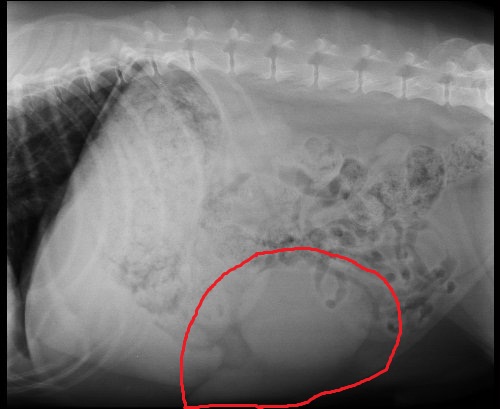

Here is the X-Ray image of the mass - at least I believe that is his spleen and mass --- the spleen should be about a third of that size or smaller:

So the mass turned out to be what I expected --- It is (was) a hematoma, the best of all cases! Basically, it was a large, grapefruit-sized blood clot attached to his spleen. With the removal of his spleen and the mass the procedure was curative of any concern related to the mass. Phew!

Today I took Jedi down to the surgical center and met with surgical team. They indicated they surgery is performed a lot and the only real complications they encounter (and rarely at that) are heart arrythmias during or within 24 hours of the surgery and excessive bleeding. But they reassured these rarely happen and they monitor for the arrythmias overnight. They would keep him for 2 days or so depending on how things go. They reviewed the X-Rays with me, and agreed that they saw no visible problems in his bones or joints, they saw no signs of cancer, though that doesn't mean it isn't and that overall he appears healthy. They gave me the estimate and said they could do that afternoon. So I agreed.

Around 5:30 this evening they called as the surgery was over and everything went well. They removed the mass (and spleen) and said the extra mass was the size of a grapefruit and they're sending it off for a biopsy. They also sent off a portion of his liver and pancreas as they showed some lesions, though they felt they were not cancerous they wanted to be sure. So the hard part is over, the surgery is done, healing has started and now we need to wait until I bring him home and for the biopsy results.

Today was Jedi's ultrasound and the news is more or less good for Jedi and bad for my wallet...

• The tumor itself - does not look like any of the 3 conditions I previously mentioned - though it still could be any of them. It does not have the shape of a hemangiosarcoma, which is good, but it does not rule out other sarcoma's (malignant tumors).